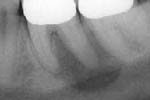

Revisionsbehandlung eines Unterkiefermolaren (37) vor geplanter Überkronung (Dr. Maik Göbbels) Download